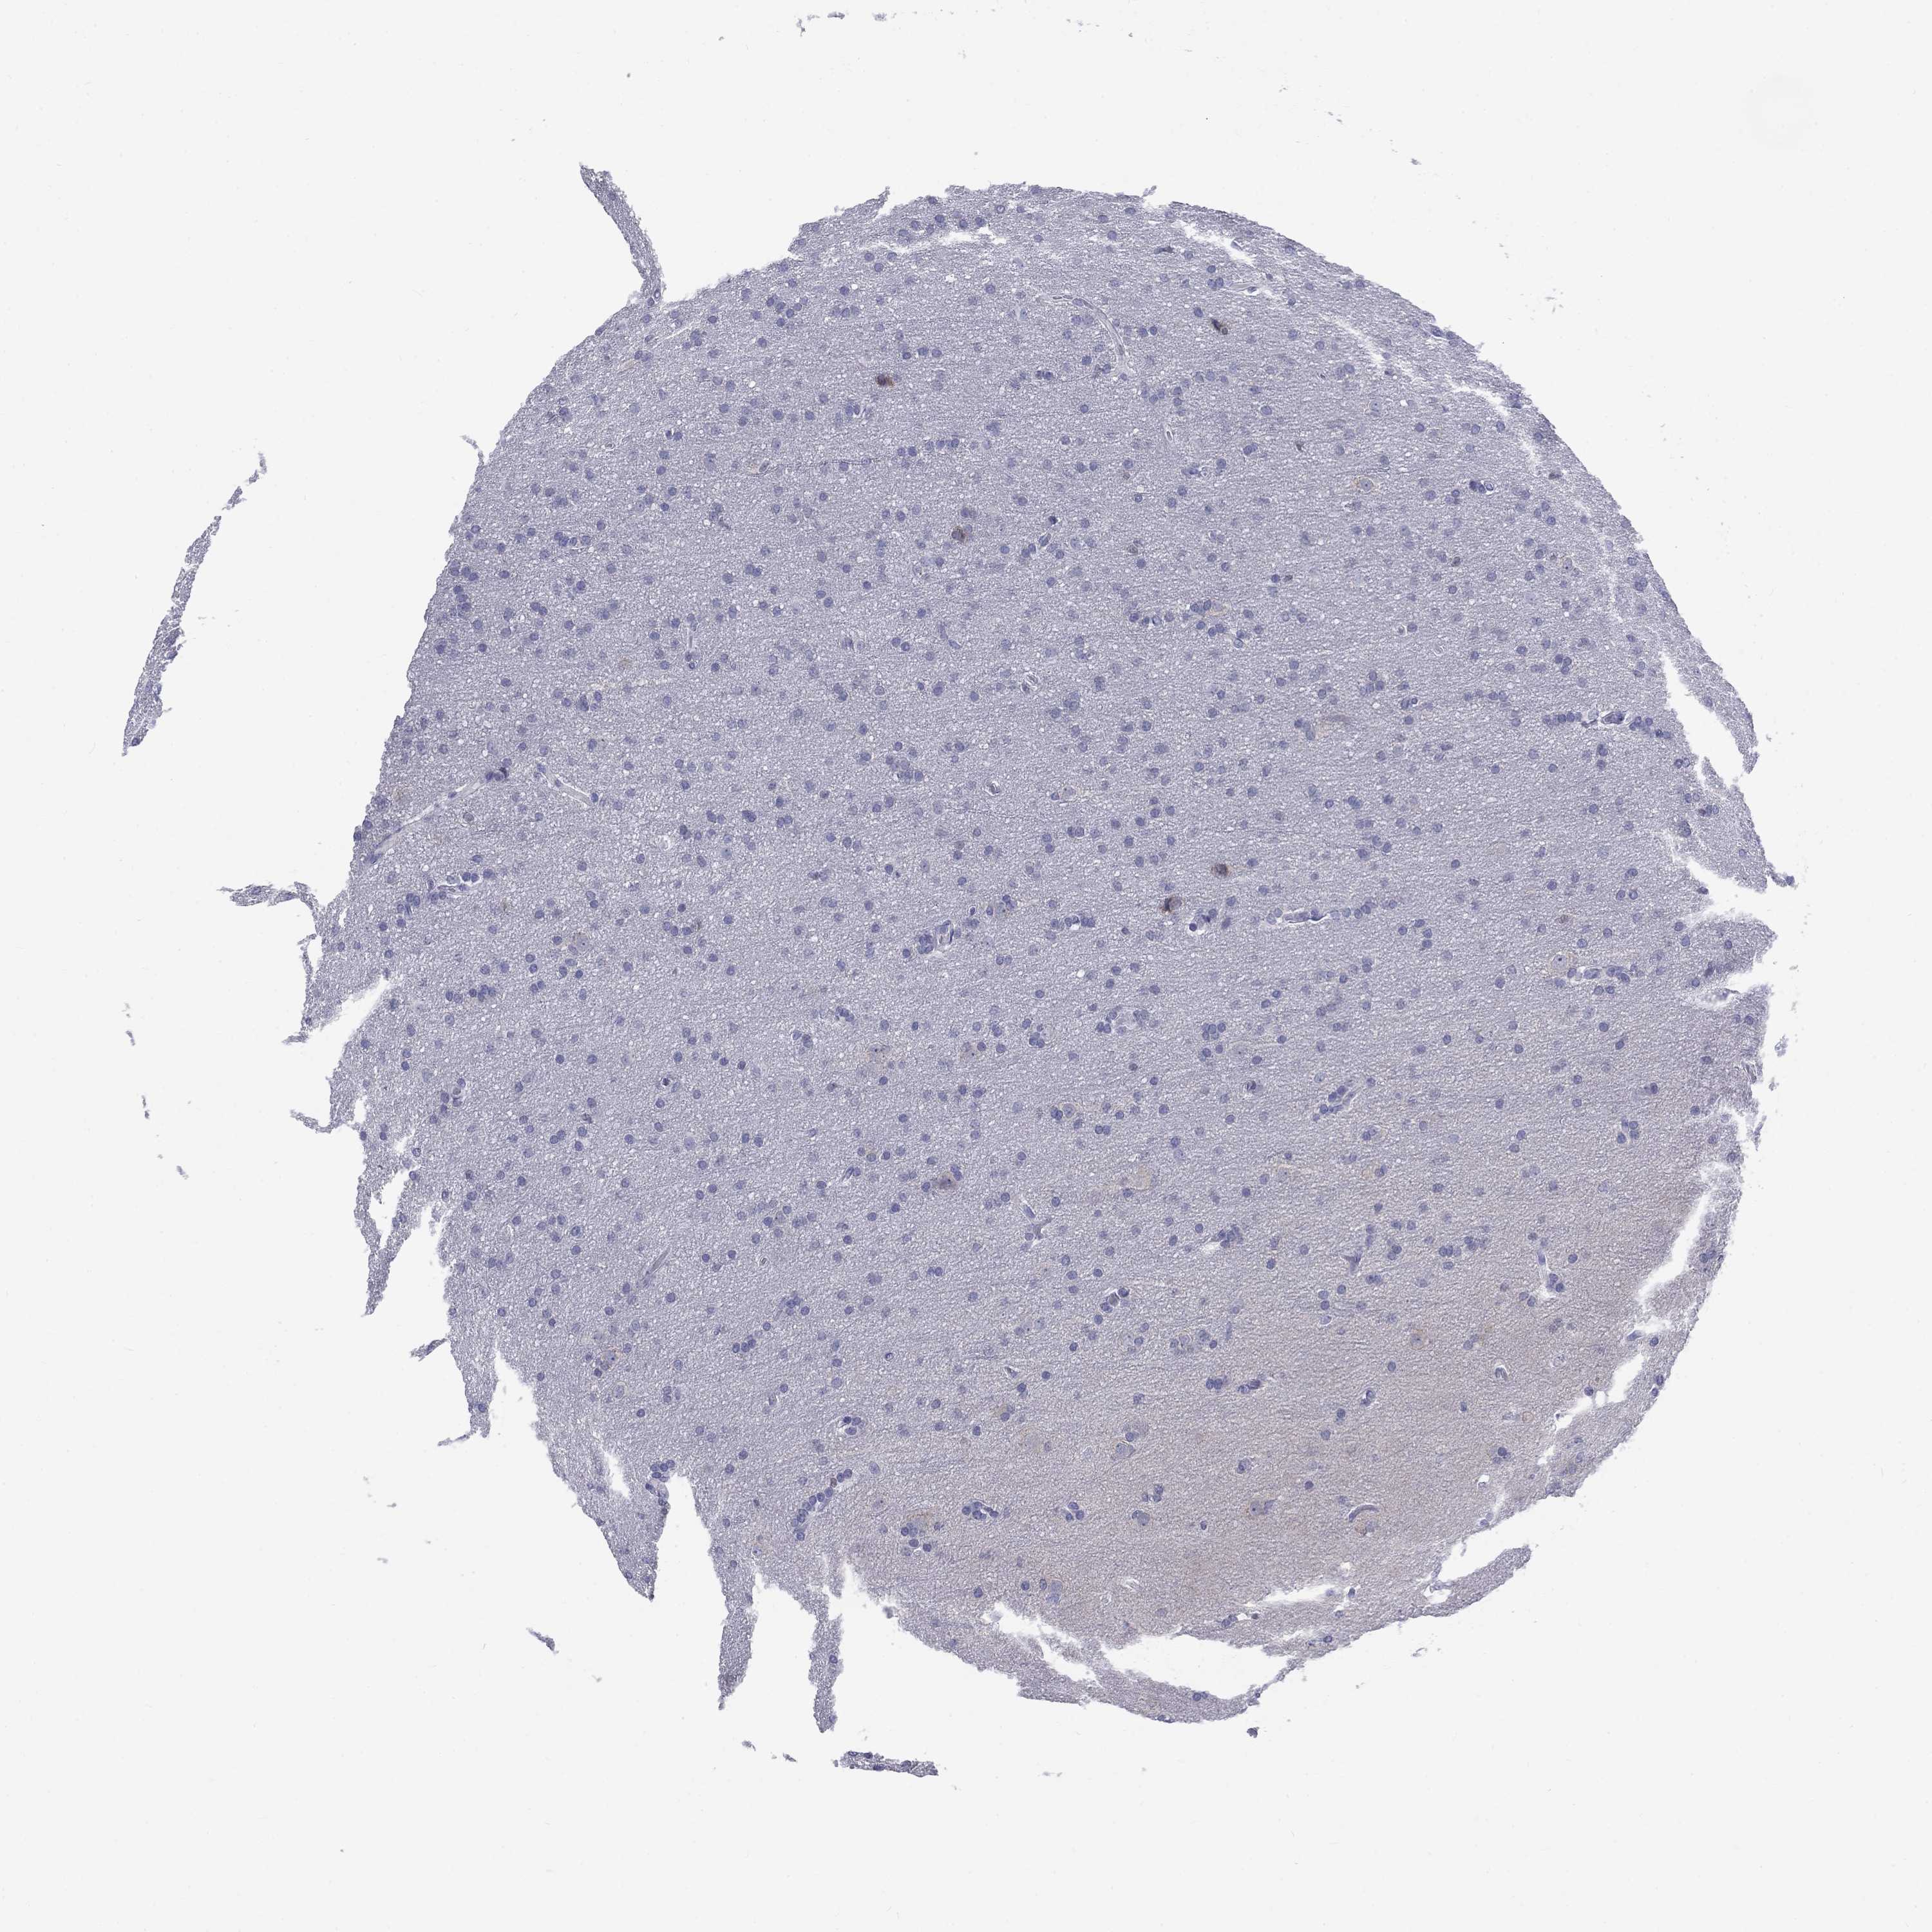

GLIOMA - Protein expressioni

A mouse-over function shows sample information and annotation data. Click on an image to view it in a full screen mode. Samples can be filtered based on level of antibody staining by selecting one or several of the following categories: high, medium, low and not detected. The assay and annotation is described here.

Note that samples used for immunohistochemistry by the Human Protein Atlas do not correspond to samples in the TCGA dataset.

Antibody stainingi

Antibody staining in the annotated cell types in the current human tissue is reported as not detected, low, medium, or high, based on conventional immunohistochemistry profiling in selected tissues. This score is based on the combination of the staining intensity and fraction of stained cells.

Each image is clickable and will lead to virtual microscopy that enables deeper exploration of all samples and also displays staining intensity scores, fraction scores and subcellular localization as well as patient and tissue information for each sample.

Antibody HPA068138

Antibody HPA071902

Staining

High

Medium

Low

Not detected

Intensity

Strong

Moderate

Weak

Negative

Quantity

>75%

75%-25%

<25%

None

Location

Nuclear

Cytoplasmic/membranous

Cytoplasmic/membranous,nuclear

Glioma, malignant, Low grade

Glioma, malignant, High grade

Glioma, malignant, NOS